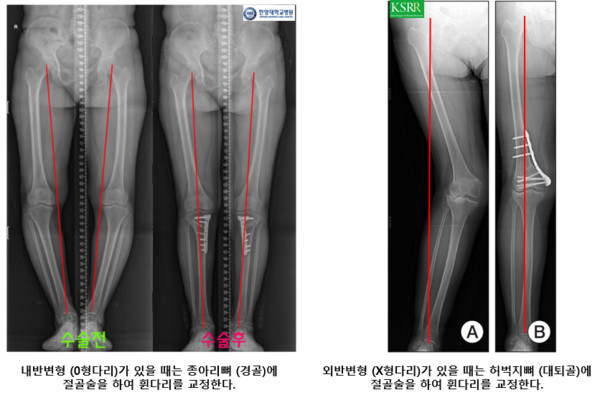

그리고 다리를 재정렬시키기 위한 절골술은 하지의 정렬 상태가 정상에 비해 비정상적으로 틀어져있을 때 시행합니다. 그림에서 보시는 것처럼 하지가 정상 정렬일 때는 체중이 전달되는 선(빨간선)이 무릎의 정중앙으로 내려갑니다.

이렇게 되면 내측과 외측에 비교적 균일하게 잘 배분되는데 내반 또는 외반 정렬일 때는 체중이 내측 또는 외측에 집중됩니다. 만약 집중되면 쪽에 병변이 있게 된다면 (예: 내반정렬일 때 내측 무릎 관절의 관절염) 악화될 가능성이 높아서 정상정렬을 만들기 위한 절골술을 고려합니다. 다만 일반적으로 반월 연골판의 파열만으로는 고려하지 않으나 말씀드린 것처럼 관절염의 진행이 관찰될 때 고려합니다.

엠비드의 경우 골반쪽 뼈라고 기사에 나왔는데 아마도 허벅지뼈(대퇴골)을 이야기하는 것 같았습니다. 일반적으로 내반변형 일때는 종아리뼈(경골)에 절골술을 시행하여 교정하고, 외반변형일때는 허벅지뼈에 절골술을 하는 것이 일반적입니다.